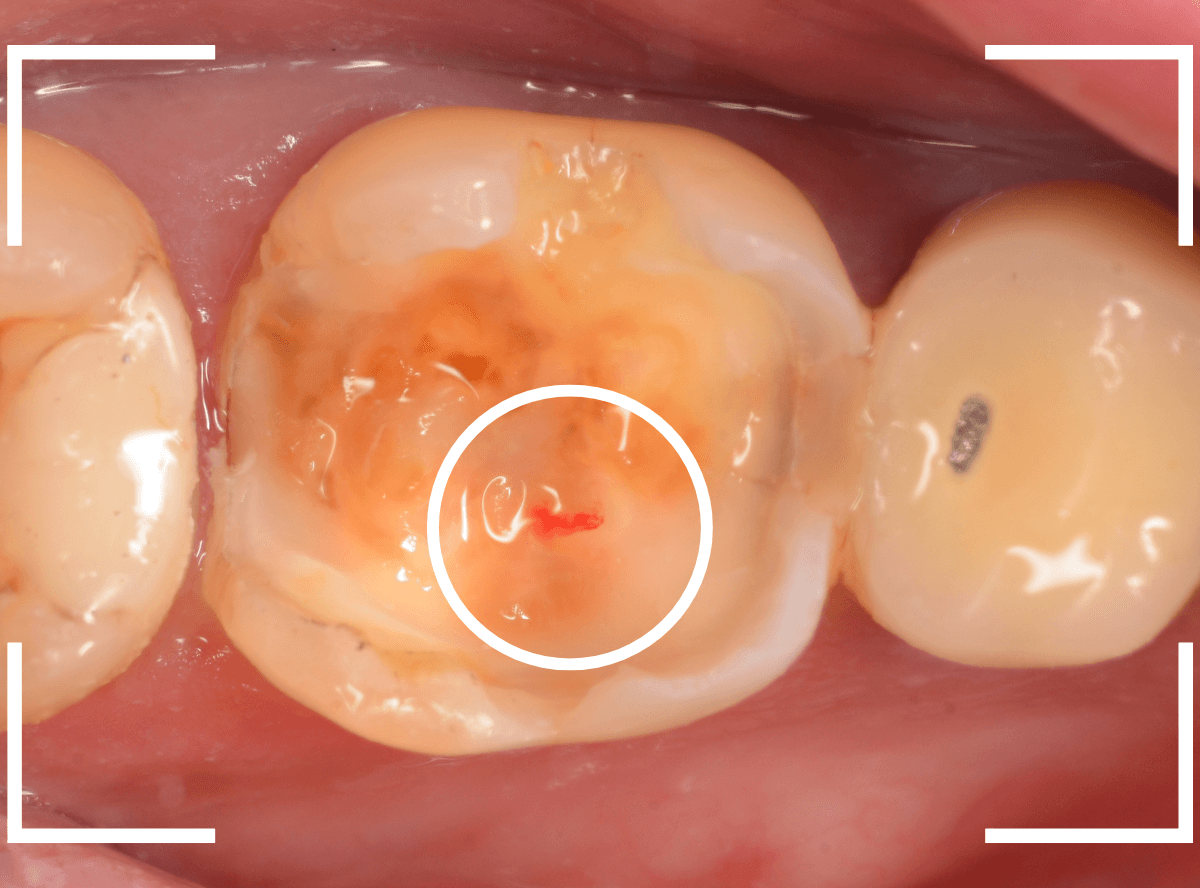

Case.20 劣化したレジン側面から進行した虫歯

「つめものが欠けたまま長期間放置して、歯がしみる」という訴えで来院された患者さんさんです。

拝見すると、劣化したレジンが欠けて、中で虫歯になっているのがわかります。

・欠けたまま長期間放置した

・しみるという自覚症状がある

事から、中で深い虫歯になっている事が想像されます。

レントゲン写真で確認します。

赤い線がレジンが入っている部分。

青い線が歯の神経です。

かなり神経の近いところまでレジンがつめてあるのがわかりますが、虫歯が側面からどの程度進んでいるのかはよくわかりません。

レントゲン写真だけみると、治療の必要がなさそうにも見えます。

このように、初見では虫歯になっている事が明らかなのに、レントゲン写真ではまったくわからないとう事もあります。

レジンを外しながら、虫歯を確認します。

慎重にレジンを除去しましたが、途中で露髄(神経が露出する事)しました。

歯の神経の中には、血管も含まれているので、神経が露出すると、このように出血します。

「しみる、痛い」などの明確な強い症状がある場合、このような状況の事が多いです。

今回は出血量が多く、神経を除去する治療(抜髄)の可能性が高いとも感じましたが、できる限り神経を保存する方法を取ることにしました。

神経を保護するお薬をつめて蓋をしてしばらく経過観察します。

神経を除去すると、治療期間が長引くうえに、歯の寿命がとても短くなってしまいます。

できるだけ歯の神経を残すためには、症状が出てからの歯科受診ではなく、定期的なメンテンナンス受診を続けるようにしてください。